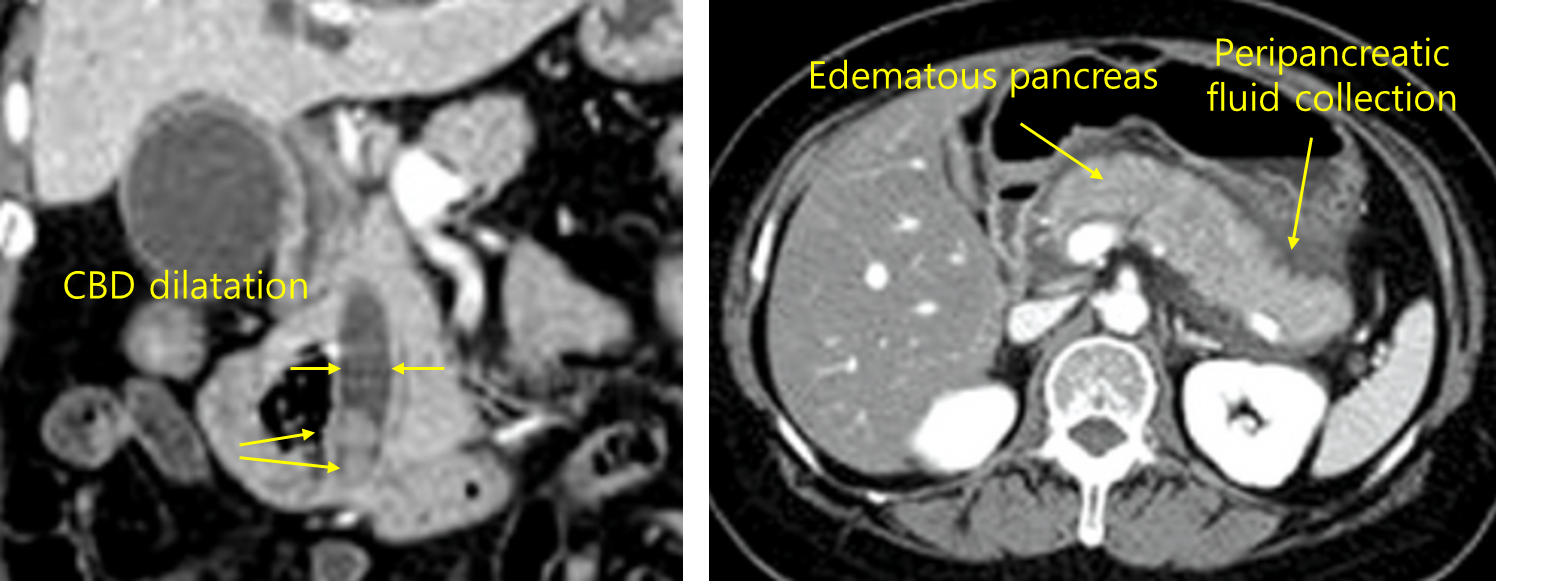

52세 여자가 2일 전부터 윗배가 아프다고 병원에 왔다. 통증은 등으로 뻗치고 갑자기 시작하여 악화되었다고 한다. 1개월 전에도 유사한 통증이 있었다고 한다. 혈압 140/90mmHg, 맥박 90회/분, 호흡 22회/분, 체온 38.2℃이다. 복부 진찰에서 장음은 감소되고 윗배에 압통이 있다. 혈액검사 결과는 다음과 같다. 복부 컴퓨터단층촬영 사진이다. 적합한 치료를 고르시오 (한 가지).

백혈구 14,600/mm3, 혈색소 14.3g/dL, 혈소판 244,000/mm3, 총단백질 8.0g/dL, 알부민 3.8g/dL, 총빌리루빈 4.6mg/dL, 직접빌리루빈 2.9mg/dL, 아스파르테이트아미노전달효소 243U/L, 알라닌아미노전달효소 250U/L, 알칼리인산분해효소 390U/L, 감마글루타밀전달효소 430U/L, 프로트롬빈시간 13초(참고치, 12.7~15.4), 아밀라제 980U/L, 리파제 1,120U/L

Img | CT: 담관 확장 및 담관내 담석, 췌장 종대 및 불명확한 경계 |

• 급성 상복부 통증, 등으로 방사되는 통증, 혈액검사 상 amylase와 lipase 상승으로부터 급성 췌장염을 의심할 수 있다. CT 상에서 담관 내 담석, 총담관 및 간내담관의 확장이 관찰되므로 담석이 급성 췌장염의 원인이 되었을 것으로 추정할 수 있으며, 백혈구 상승, 간효소 수치의 상승 등 담관염의 소견도 확인된다.

• 담석에 의한 급성 췌장염은 내시경역행쓸개이자조영술로 담석을 제거하여야 한다.

진단 | • US: 담석, 담관확장 확인 • CT: 췌장 실질의 edema, 췌장 근처 조직의 inflammation |